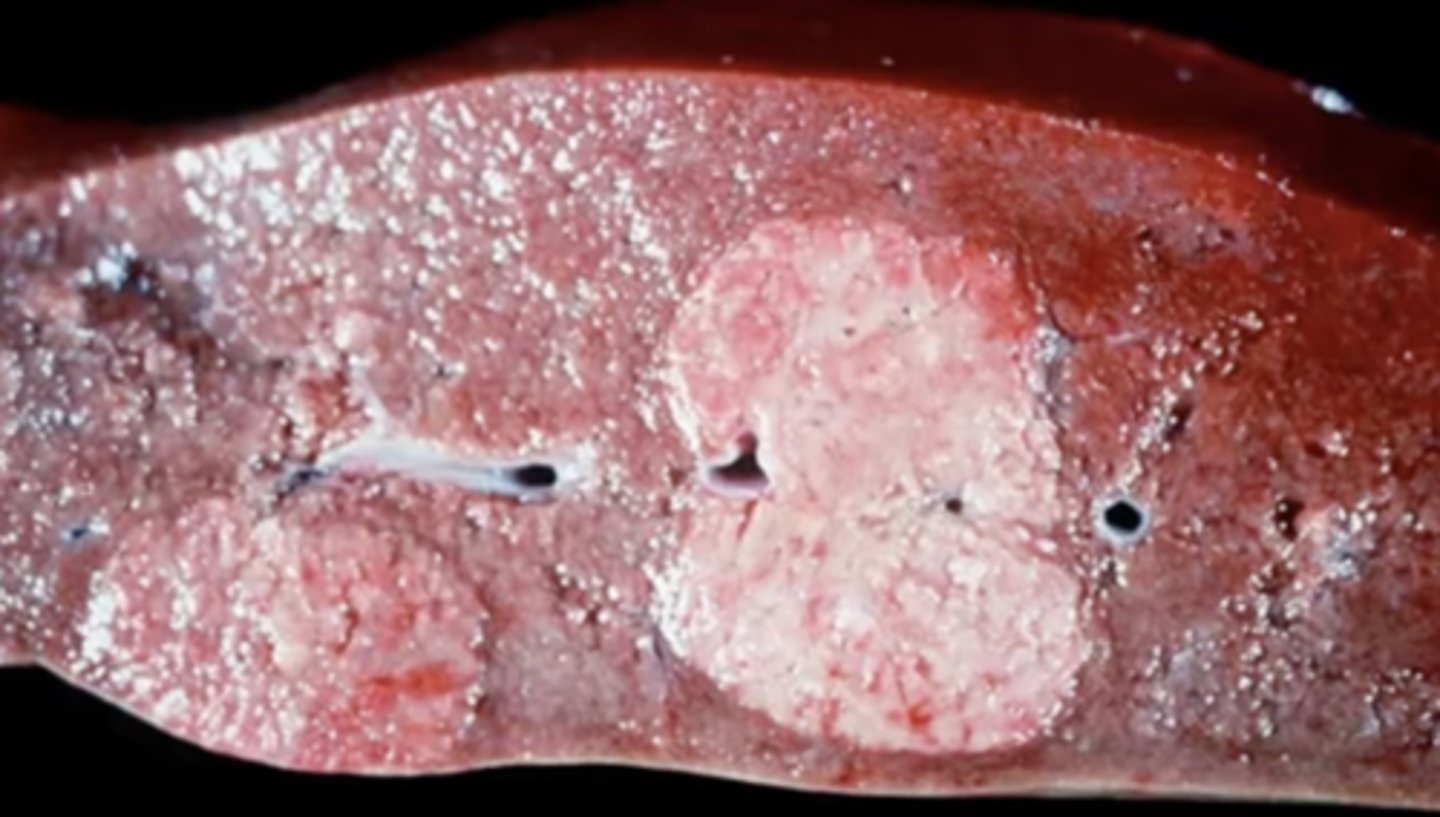

Milk spots - scars from ascaris suum migrating through the liver

Pig liver: What are these white sunken spots known as ?